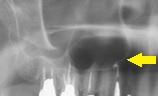

レントゲンではこの線が上顎洞の最下部として写ります。人によっては鼻の穴と通じる上顎洞が大きい人もいて、上の奥歯の根がとびだしている人がいます。

レントゲンでは上顎洞の大きさ本当に人それぞれで大きなひとであれば糸切り歯まで広がっている人も見たことがあります。